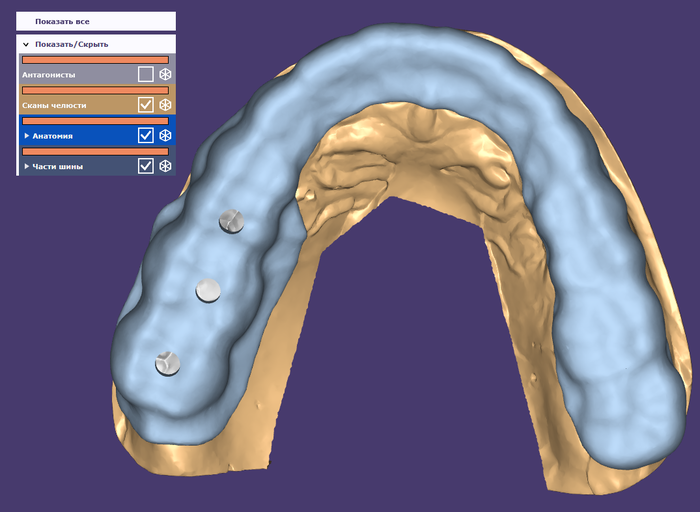

Мужчине были установлены и спротезированы (временными коронками) имплантаты в другой клинике. После этого он пропал на несколько лет, не закончив полностью свое лечение. Явился лишь тогда, когда почувствовал «дискомфорт».

Кроме несостоятельности старых коронок и пломб, патологической стираемости зубов и т.д. - все эти годы сильно страдала гигиена.

Так выглядят временные (пластмассовые) коронки после их снятия. Они просто утопают в говне налёте. (К слову – поверхность временных коронок отлично собирает на себе налёт, чего в таком количестве не бывает на постоянных, сделанных из керамики.)

Но пациента, видимо, это не особо то беспокоило. Если, даже, выпавшие пару лет назад временные коронки на противоположной стороне его не шибко волновали.